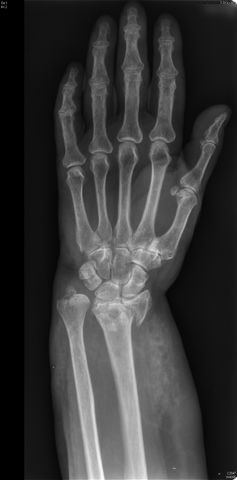

Carpo normal